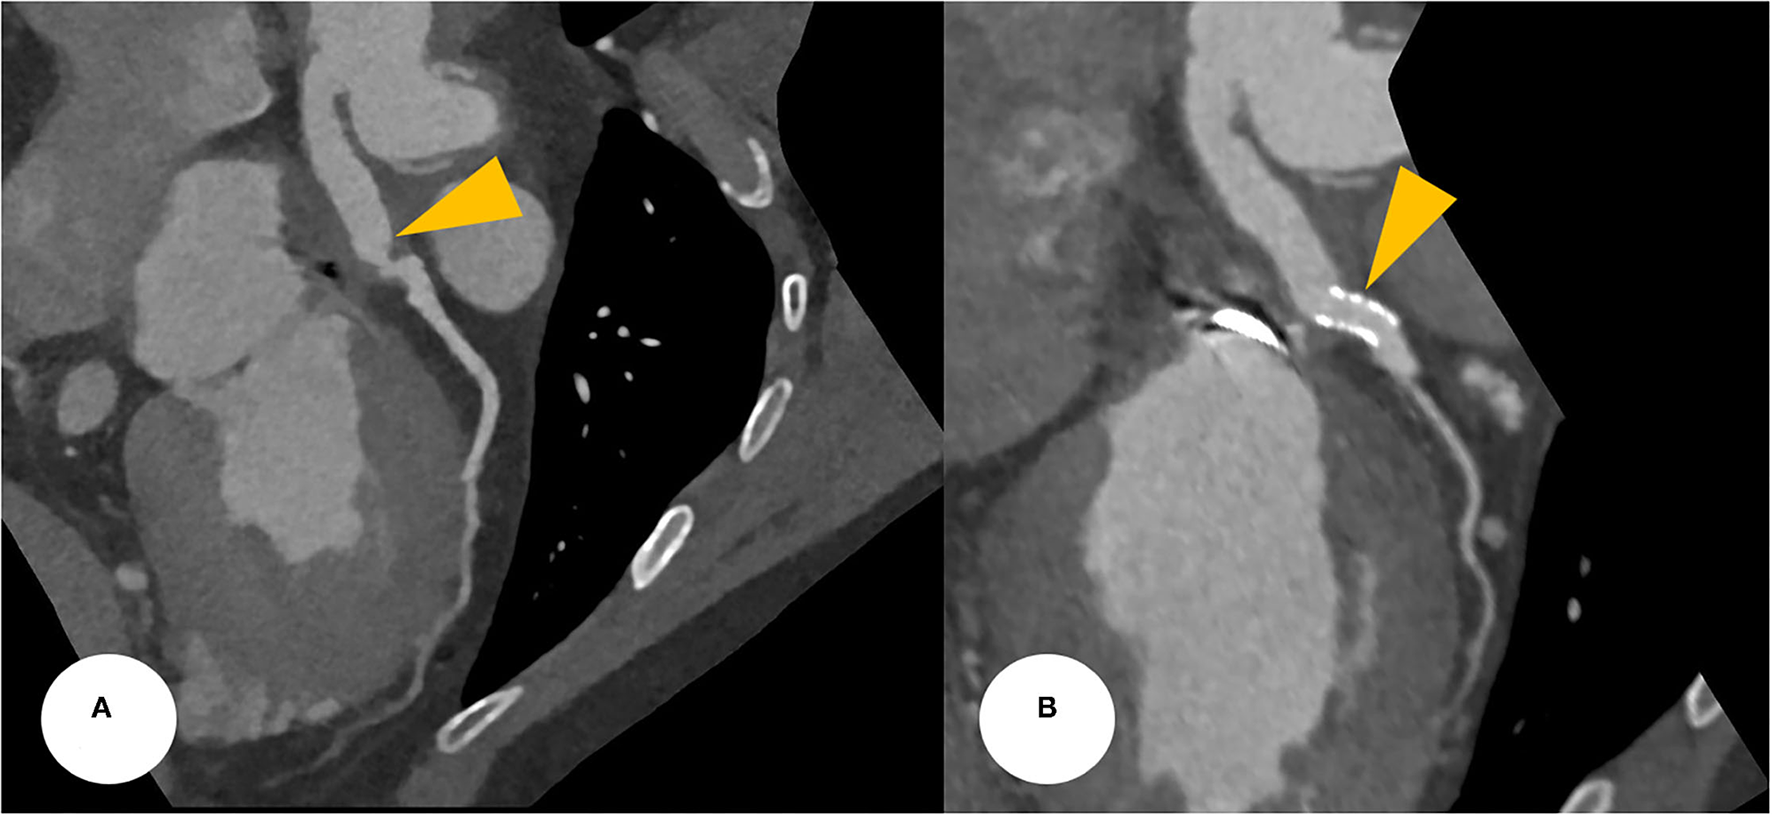

Figure 3

(A) CCTA at the postoperative period found a focally narrowed and kinked lesion at the anastomotic site between the Cabrol-type graft and LMCA (a yellowish arrowhead). (B) After a successful PCI, CCTA was evaluated, revealing a stent deployment state between the conduit and LMCA with good patency (yellowish arrowheads). CCTA, coronary computed tomography angiography; LMCA, left main coronary artery; PCI, percutaneous coronary intervention.

His vital signs were as follows: temperature, 36.3°C; heart rate, 75 beats/min; respiratory rate, 20 breaths/min; and blood pressure, 110/80 mmHg. A 12-lead electrocardiogram showed normal sinus rhythm with a right bundle branch block. However, the electrocardiogram also revealed ST-segment elevation in aVR and V1, with ST-segment depression in lead I, II, and aVL and precordial leads V4–6, suggesting LMCA occlusion (Supplementary Figure 1). Chest radiography showed mild cardiomegaly and definite evidence of prior median sternotomy and valvular replacement (Supplementary Figure 2). Laboratory tests showed elevated levels of troponin I (0.887 ng/mL; reference: 0–0.050 ng/mL) and pro-brain natriuretic peptide (1,549 pg/mL; reference: 0–300 pg/mL). The patient was administered warfarin, therefore, the prothrombin time–international normalized ratio was estimated to be 1.90. A two-dimensional transthoracic echocardiogram revealed a well-functioning AoV with akinetic movement at the anterior and anteroseptal parts of the myocardium, and a left ventricular ejection fraction of 36.3%. We reviewed the findings of previous coronary computed tomography angiography to obtain detailed anatomical information about the focal stenosis at the anastomotic site between the LMCA and the aortocoronary graft (Figures 2, 3A). Since the patient was diagnosed with non-ST-segment elevation acute coronary syndrome, PCI was performed.

After the PCI procedure, the patient received optimal medical therapy, including dual antiplatelet agents–aspirin (100 mg/day) and clopidogrel (75 mg/day), an oral anticoagulant–warfarin (1 mg/day), a high-intensity statin–rosuvastatin (20 mg/day), a beta-blocker–bisoprolol (2.5 mg/day), and an angiotensin II receptor blocker–valsartan (40 mg/day). The post-PCI coronary computed tomography angiography demonstrated a well-expanded and well-apposed stent strut at the anastomotic site (Figure 3B). His anginal symptoms dramatically improved, and he was successfully discharged from our hospital.